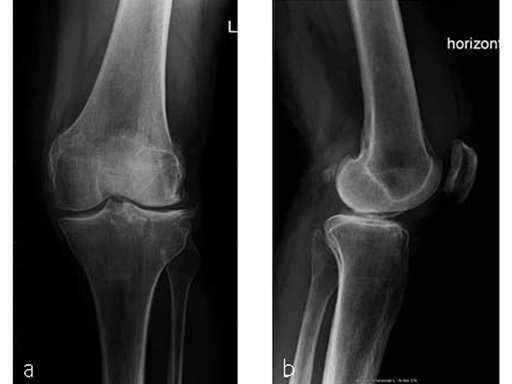

A 70-year-old female patient had an accident while hiking. Osteoporosis was preexisting but with asymptomatic moderate degenerative osteoarthritis of the knee with chondrocalcinosis of the lateral compartment (Fig 1 and 2).

The area was functional soon after treatment (Fig 3), and the patient was able to experience weight bearing of 20 kg for the first 6 weeks. She was completely pain free after 6 weeks (Fig 4) with excellent muscular function and coordination, therefore unlimited weight bearing after the first follow-up was enabled.